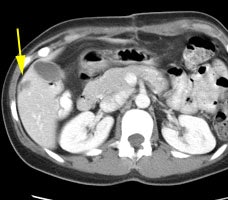

Initial staging for extrahepatic metastases: The patient below underwent FDG PET imaging to assess for extrahepatic metastatic disease prior to definitive surgical intervention. The PET exam demonstrates uptake within two hepatic metastases (black arrows on PET scan and yellow arrows on CT images) and in the patients primary colon cancer (blue arrow on PET scan and white arrow on CT image). No other sites of abnormal tracer uptake were identified which supports surgical intervention in this case. |